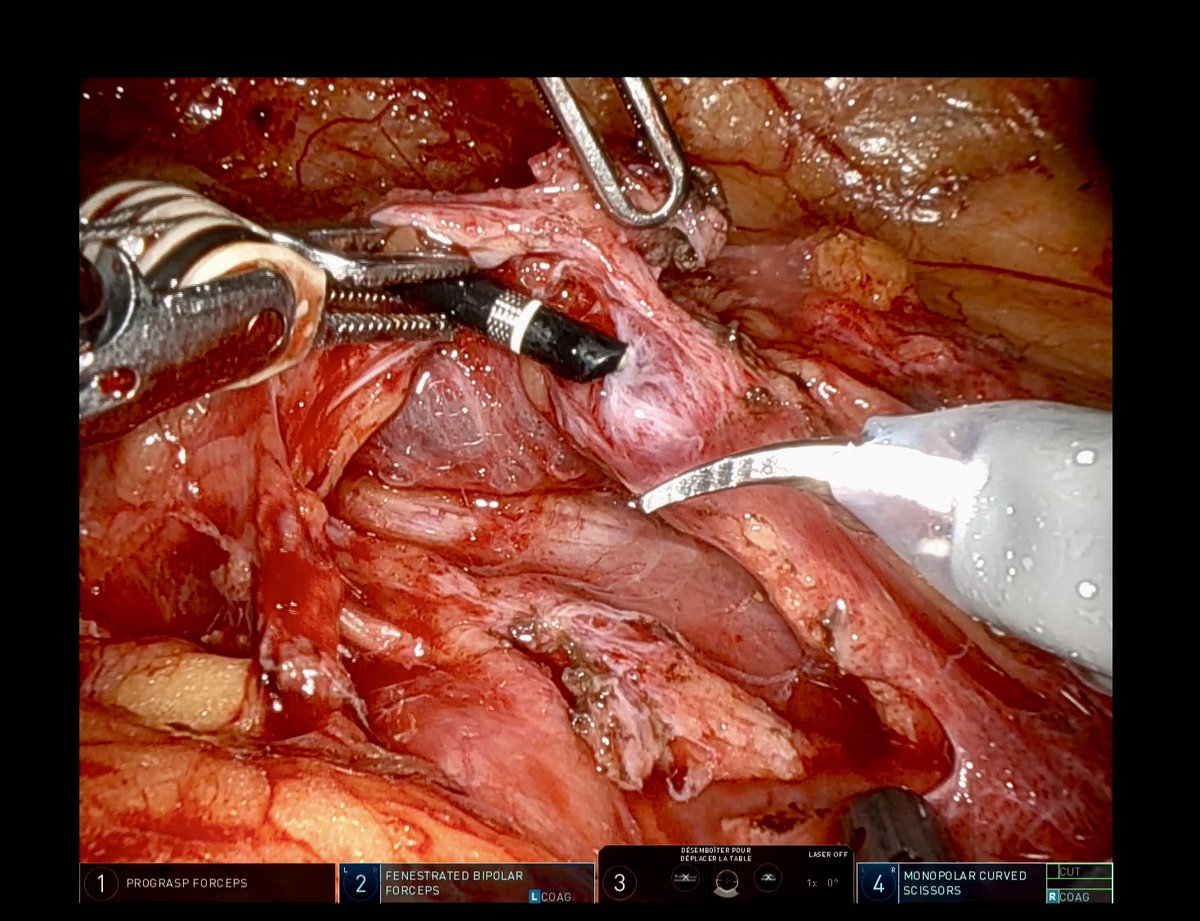

First robotic buccal mucosa graft ureteroplasty for ureteral stricture after ureteroscopy Hôpitaux @HopPitieSalpe 🦾😷✌🏽